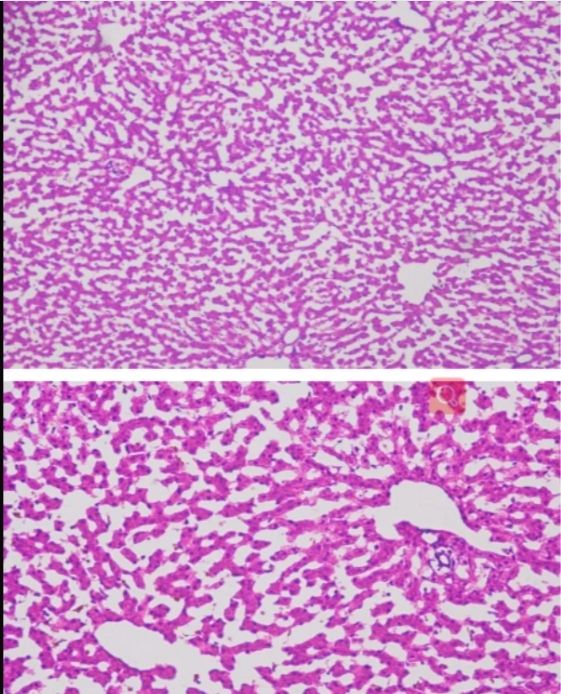

今天普拉特澤生物繼續(xù)跟大家一起學(xué)習(xí)新的實(shí)驗(yàn)——冰凍切片,是一種重要的實(shí)驗(yàn)技術(shù),它在低溫條件下使組織快速冷卻到一定硬度,然后進(jìn)行切片。這種技術(shù)具有簡便、快速、組織變化小以及能夠保存脂肪和類脂等成分的優(yōu)點(diǎn),被廣泛應(yīng)用于生物學(xué)、醫(yī)學(xué)等領(lǐng)域。本文將詳細(xì)介紹冰凍切片實(shí)驗(yàn)的原理以及其在各個(gè)領(lǐng)域的應(yīng)用。 冰凍切片實(shí)驗(yàn)原理以及應(yīng)用由普拉特澤生物組織染色檢測平臺(tái)總結(jié)分享,組織染色檢測平臺(tái)為廣大科研實(shí)驗(yàn)人員提供冰凍切片外包實(shí)驗(yàn)服務(wù),先一起來學(xué)習(xí)學(xué)習(xí)什么是冰凍切片~

冰凍切片實(shí)驗(yàn)的原理基于低溫下組織的物理性質(zhì)變化。在冷凍狀態(tài)下,組織內(nèi)的水分形成冰晶,使組織變得堅(jiān)硬而易于切片。這種切片方法不需要對(duì)組織進(jìn)行固定、脫水、透明、包埋等繁瑣步驟,因此大大縮短了制片時(shí)間。同時(shí),由于避免了化學(xué)處理或加熱過程,冰凍切片能更好地保存組織的原始結(jié)構(gòu)和成分,特別是對(duì)于那些對(duì)有機(jī)溶劑或熱敏感的細(xì)胞表面抗原和水解酶。

冰凍切片在病理學(xué)診斷中具有重要應(yīng)用價(jià)值。通過冰凍切片技術(shù),病理醫(yī)生可以快速獲取組織樣本的切片,進(jìn)行顯微鏡下觀察和分析。這有助于醫(yī)生在術(shù)中快速判斷腫瘤的性質(zhì)、淋巴結(jié)是否有轉(zhuǎn)移等關(guān)鍵信息,從而指導(dǎo)手術(shù)范圍和后續(xù)治療方案。